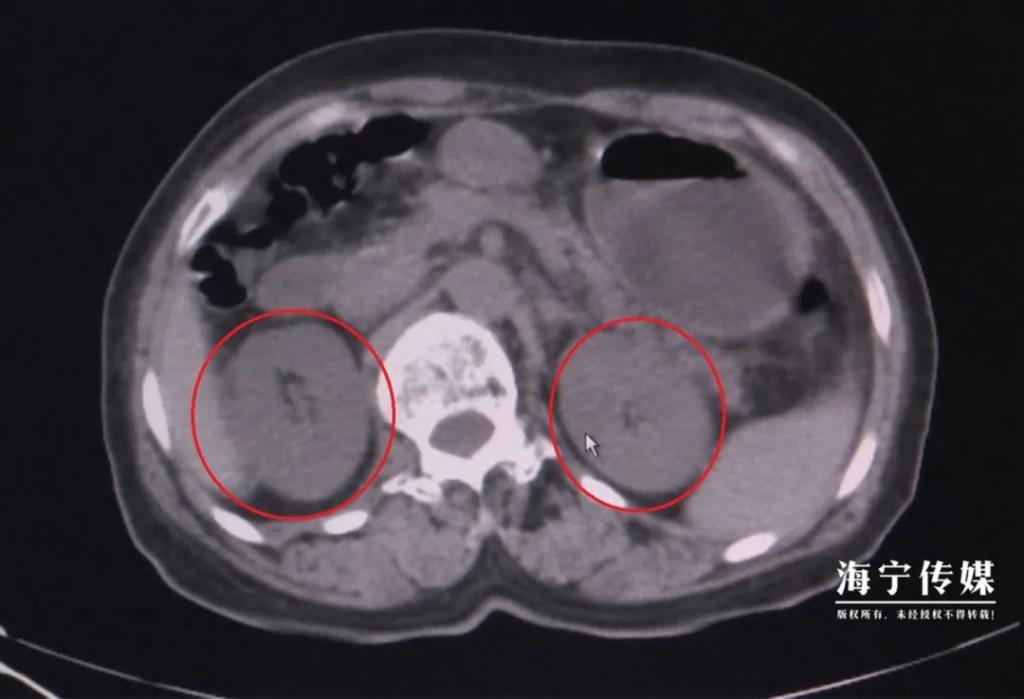

红圈部位为双肾肿胀

"这是典型的食物中毒!"鄢医生告诉记者,刀豆中含有生物碱,加热可分解。但李阿姨吃了整盘没烧熟的刀豆,毒素吸收导致急性肾功能衰竭,不能正常产生尿液,体内肌酐、尿素、氮尿酸等代谢废物无法排出。反映肾功能的肌酐指标一度飙升到 600 多,超出正常值上限的 6 倍。如不及时治疗,有突然心跳停止、血循环消失、休克的危险。住院后,李阿姨接受了血液透析治疗。